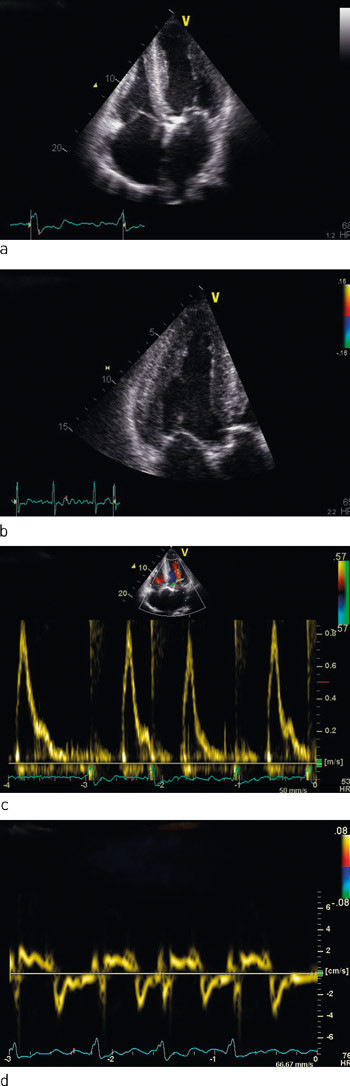

Ekkokardiografi viste moderat dilatert venstre ventrikkel med lett til moderat fortykket vegg. Endediastolisk indre diameter var 6,6 cm, septumtykkelse 1,4 cm og bakre veggs tykkelse 1,2 cm (fig 1). Venstre ventrikkels ejeksjonsfraksjon ad modum Simpson biplan var ca. 30 %. Det var tegn til forhøyet venstresidig fyllingstrykk. Aortaklaffen var trikuspid med betydelig forkalkning av alle tre kusper, redusert åpningsbevegelse og betydelig aortastenose, med areal 0,9 cm2 beregnet etter kontinuitetslikningen. Det var en liten, sentral aortainsuffisiens. Mitralklaffen hadde slanke segl og en liten insuffisiens. Det forelå biatrial forstørrelse (venstre atrium 29,5 cm², høyre atrium 20,5 cm²). Blodstrømshastigheter i mitralostiet, vevshastigheter i mitralringen og dilatert venstre atrium indikerte samlet at det forelå restriktiv fylling av venstre ventrikkel. Myokard hadde et påfallende, granulært ekkokardiografisk uttrykk, og det ble mistenkt primær myokardsykdom i tillegg til klaffefeil. Koronarangiografi viste kalk i proksimale koronarkar, men ingen signifikante stenoser.

Stressekkokardiografi med gradert dobutaminbelastning til 20 µg/kg/min viste fiksert stenose med beregnet areal 0,7 cm² (tab 1). Venstre ventrikkels systoliske funksjon var som tidligere betydelig nedsatt. Det ble ingen bedring av systolisk funksjon ved belastning.

Stressekkokardiografi med gradert dobutaminbelastning. Tabellen viser at aortastenosen er fiksert – åpningsarealet (beregnet etter kontinuitetslikningen) forblir uendret. Det fremkommer også at venstre ventrikkel mangler kontraktil reserve – slagvolumet forblir lavt og trykkgradienten over aortaklaffen stiger lite på tross av økende dobutaminstimulus. Minuttvolumet øker noe parallelt med stigende hjertefrekvens